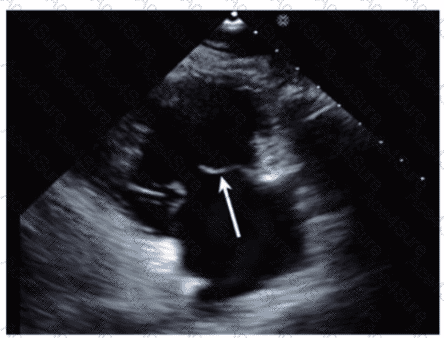

Which anatomic structure is represented by the arrow on this image?

The echocardiographic image is a four-chamber view focusing on the mitral valve apparatus. The arrow points to the anterior leaflet of the mitral valve, which is typically more prominent, triangular in shape, and located adjacent to the aortic valve in the left ventricular outflow tract region.

The posterior leaflet of the mitral valve is generally smaller, has multiple scallops, and is located posteriorly relative to the anterior leaflet. The septal leaflet is part of the tricuspid valve on the right side of the heart. The "left leaflet" is a non-specific term and not an anatomical descriptor.

This differentiation between anterior and posterior leaflets is important for understanding mitral valve pathology and for interventions such as mitral valve repair. These features are clearly explained in echocardiography texts and ASE valve imaging guidelines【12:ASE Valve Imaging Guidelines†p.180-185】【16:Textbook of Clinical Echocardiography, 6e†p.200-205】.